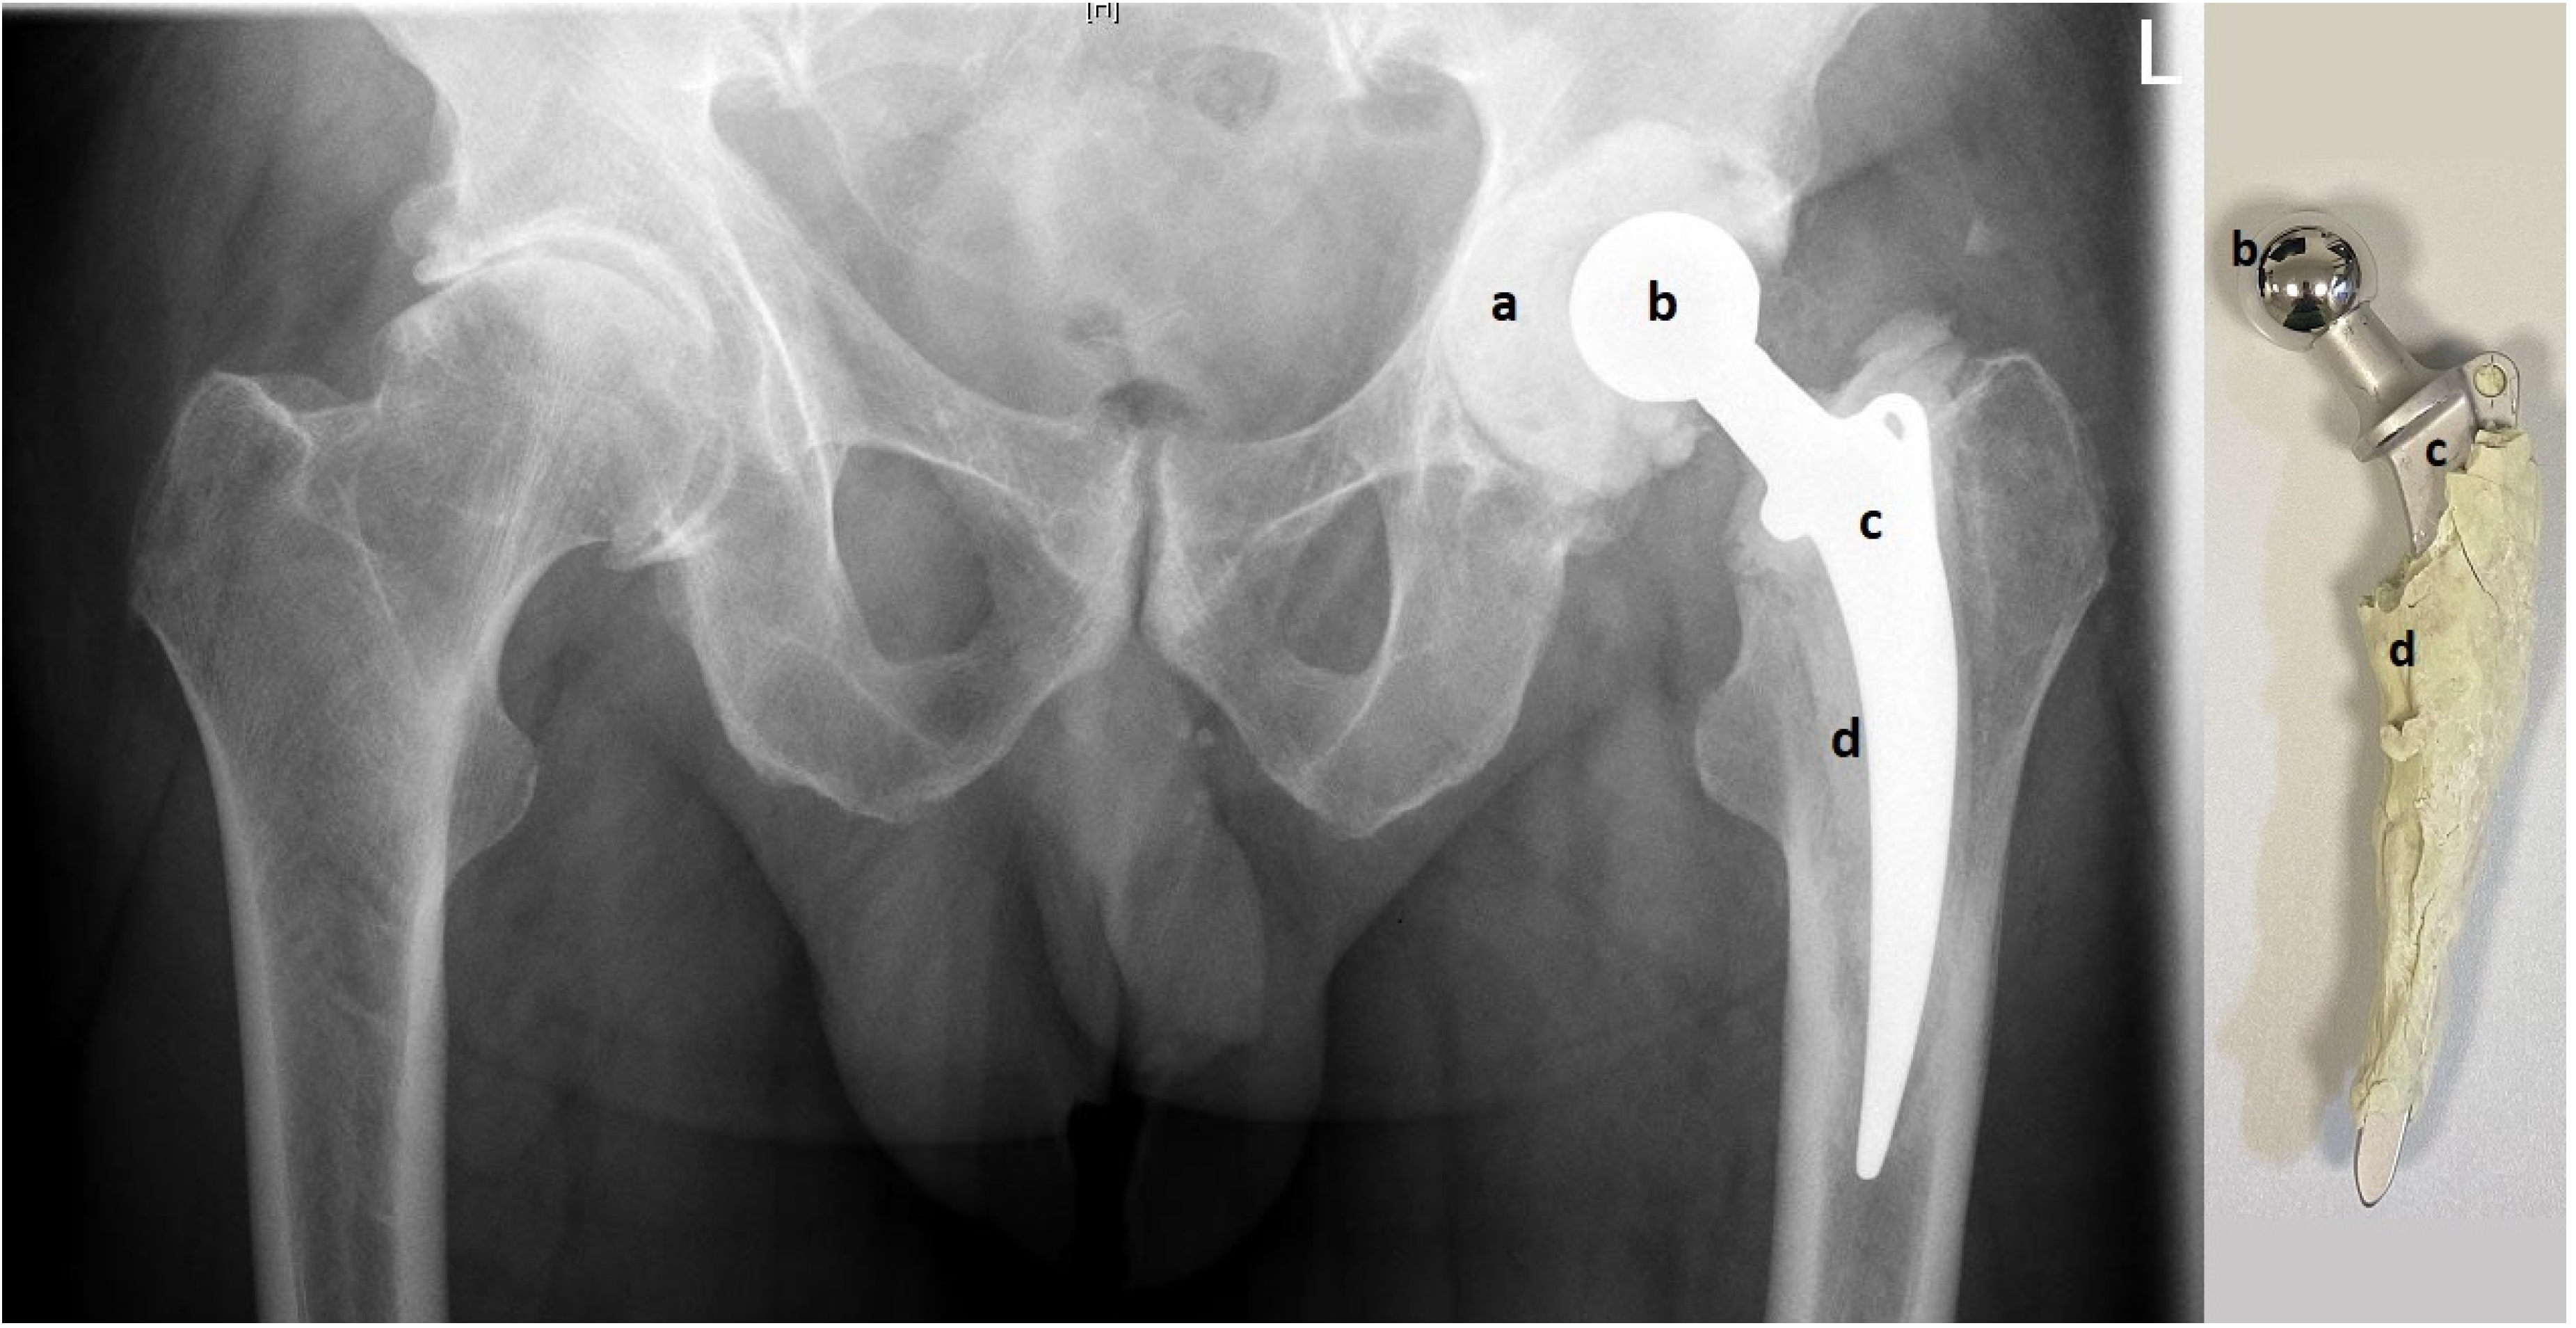

From www.researchgate.net

PROSTALAC® articulating hip spacer system. Images published with Spacers For Hip Replacement two‐stage revision hip arthroplasty is a popular approach for the treatment of late infection after total hip. preformed pmma spacers are also available in various sizes, for both hip and knee surgery, such as the ‘tecres. the following hip spacer guidelines were developed by hss rehabilitation. The use of “functional” spacers may allow patients to return to. Spacers For Hip Replacement.